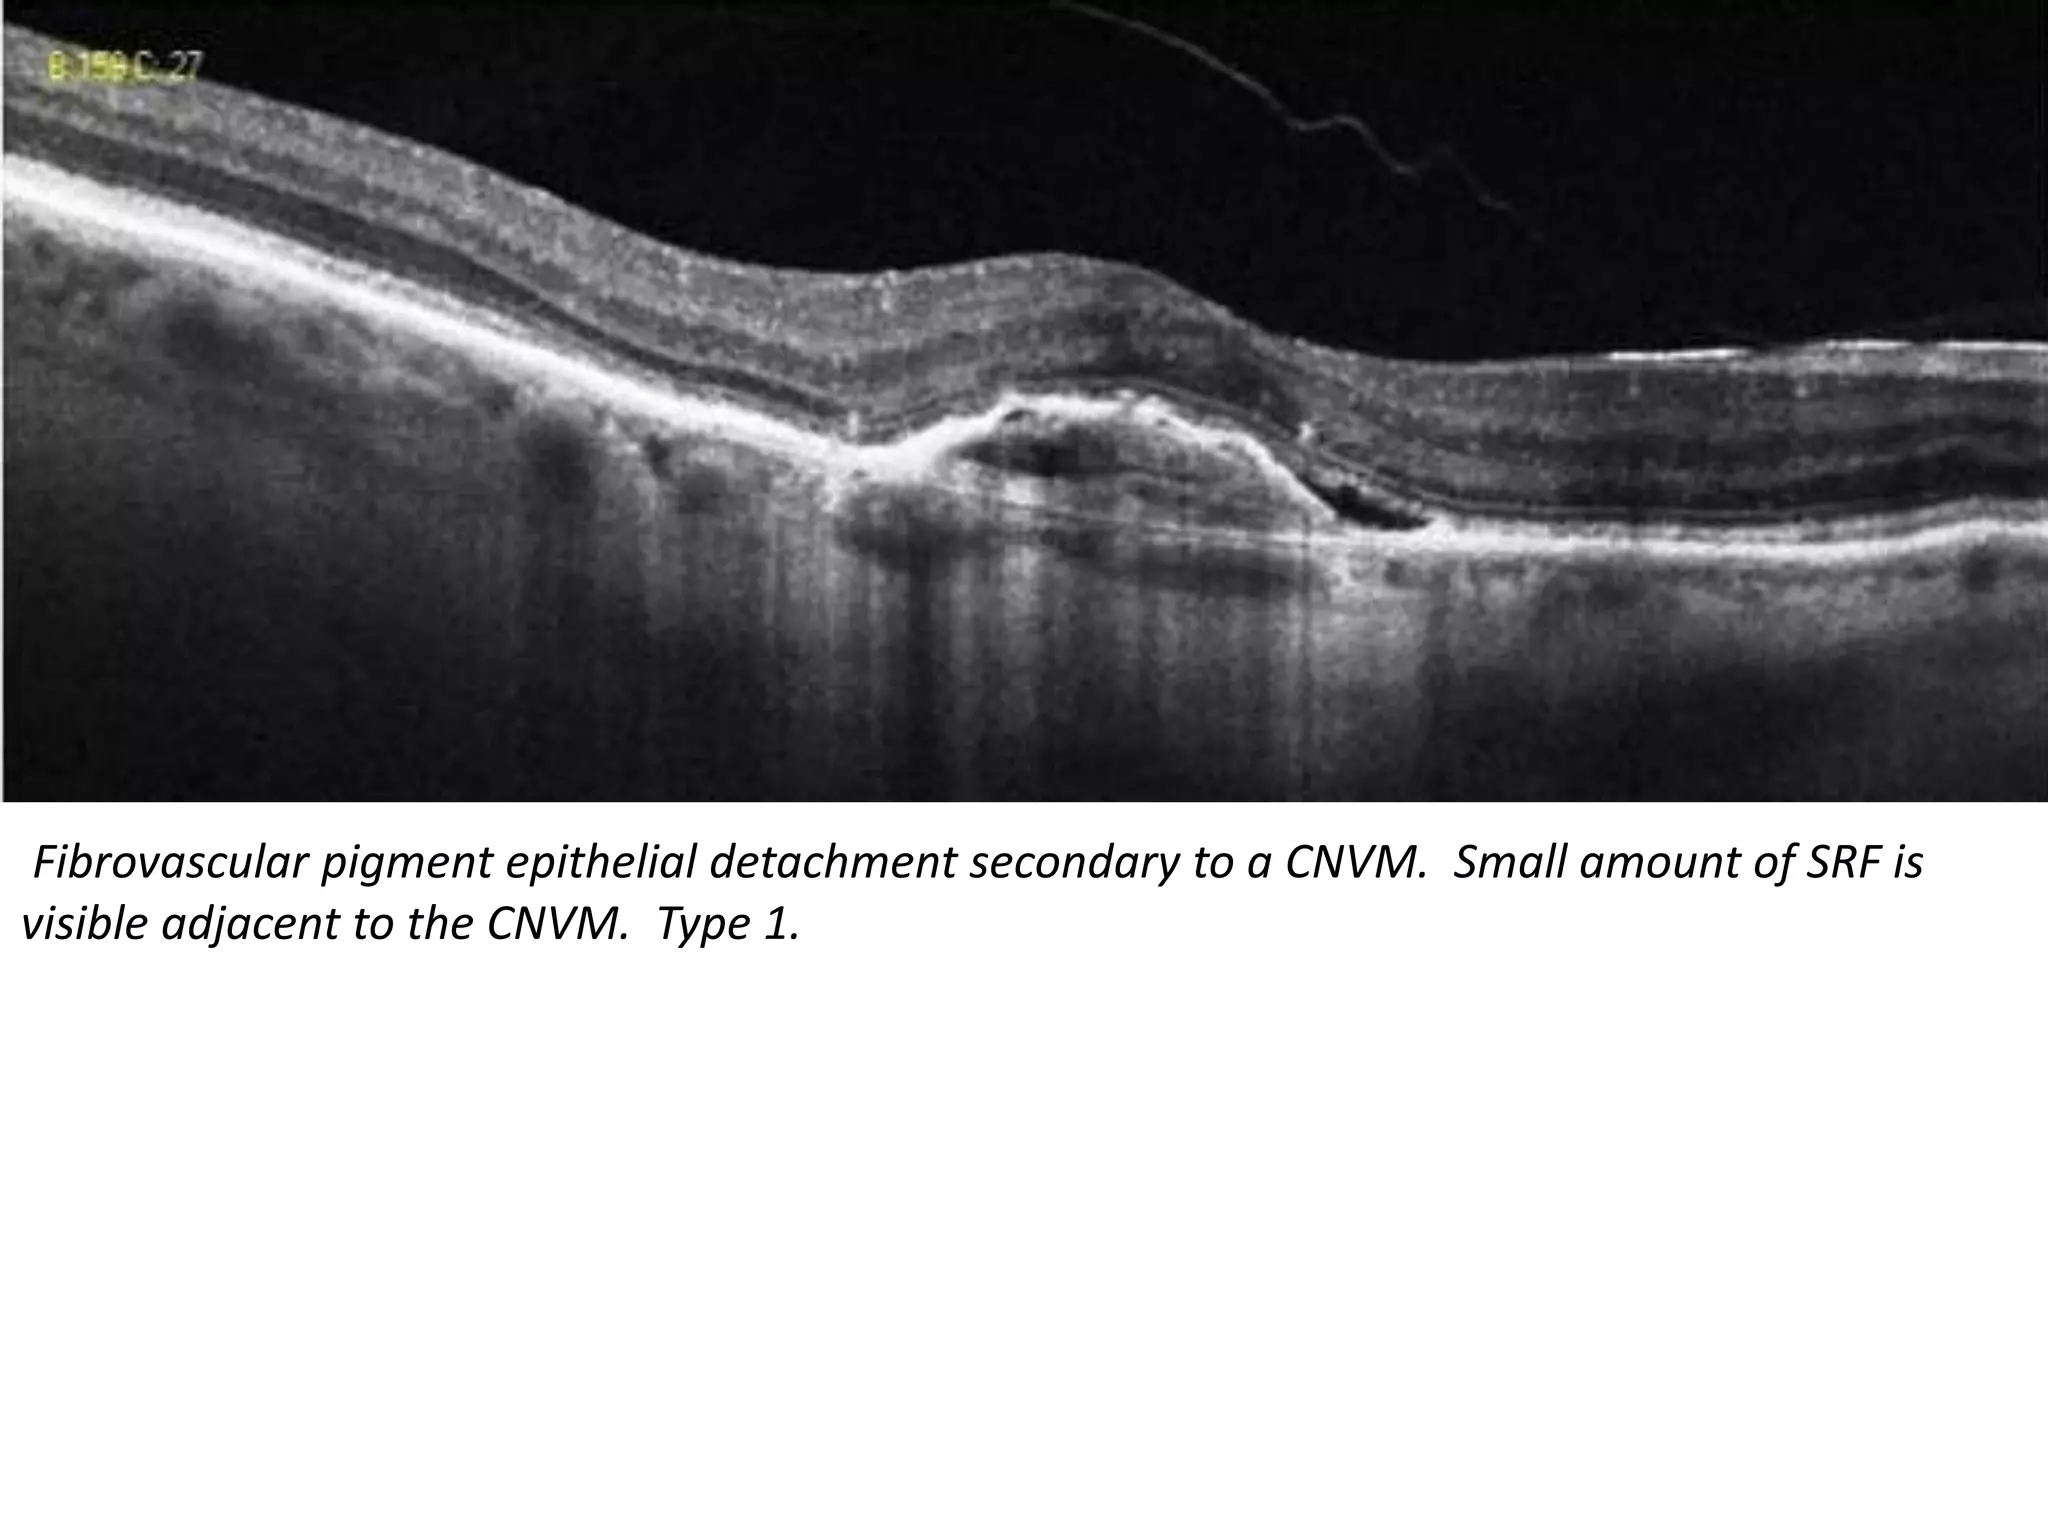

Fibrovascular pigment epithelial detachment secondary to a CNVM. Small amount of SRF is

visible adjacent to the CNVM. Type 1.

Fibrovascular pigment epithelialdetachment secondary to a CNVM. Small amount of SRF is visible adjacent to the CNVM. Type 1.